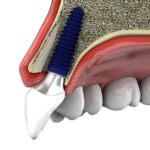

1. Nano bone matrix layer of Ca2+ -incorporated S-L-A surface

2. Fast & strong osseointegration

3. Dual check system for greater safety

Ca2+ is incorporated into the fixture structure to create a CaTiO3 nano-structure. This then forms a unique & uniform nano-structure with Ca2+ions, which activate osteoblasts in living organisms.